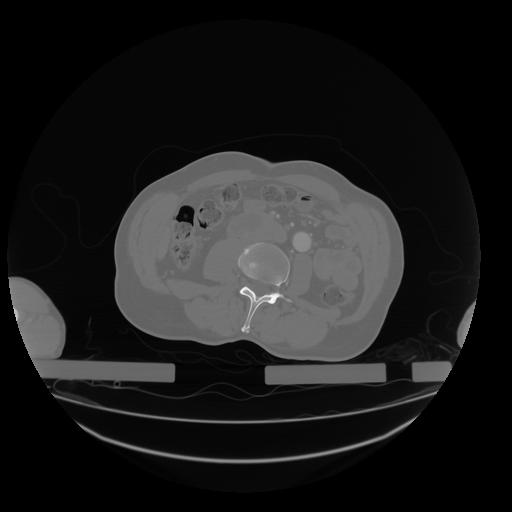

28 CUERPO,CE,Vol,2.0,CUERPO,,